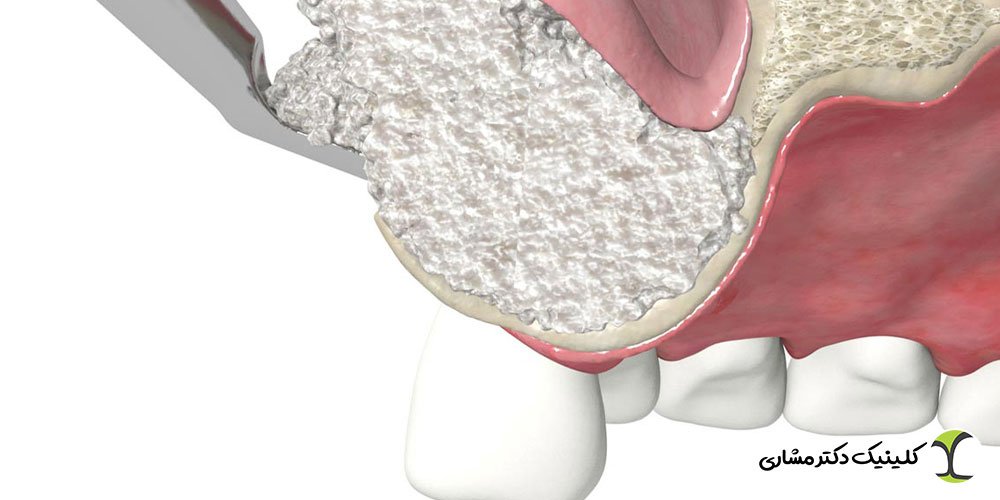

سینوس لیفت چیست؟

سینوس لیفت نوعی جراحی بازسازی استخوان است که فقط در فک بالا و در ناحیهای که سینوسهای فکی قرار دارند انجام میشود. وقتی استخوان فک بالا به دلیل تحلیل یا نزدیکی بیش از حد به سینوس حجم کافی برای کاشت ایمپلنت ندارد، جراح با بالا بردن غشای سینوس و افزودن استخوان، فضای مناسب ایجاد میکند.

مراحل سینوس لیفت شامل:

- ایجاد دسترسی جراحی به ناحیه سینوس

- بالا بردن غشای سینوس بدون آسیبرسانی

- پر کردن فضای بهوجود آمده با مواد استخوانساز

- فراهم شدن بستر مناسب برای ایمپلنت

هر دو روش سینوس لیفت و پیوند استخوان با هدف تقویت و افزایش حجم استخوان انجام میشوند تا شرایط لازم برای کاشت ایمپلنت فراهم شود. در هر دو تکنیک، از مواد استخوانی طبیعی یا مصنوعی برای بازسازی ناحیه استفاده میشود و نتیجه نهایی، ایجاد پایداری و دوام بیشتر برای ایمپلنت است.